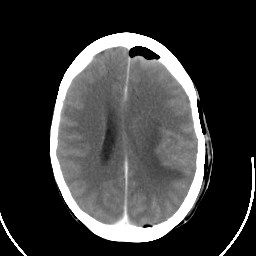

Metastatic bronchogenic carcinoma: Roentgen-ray CT (post-op) -- Slice #14

[Home][Help][Clinical] Slice 14